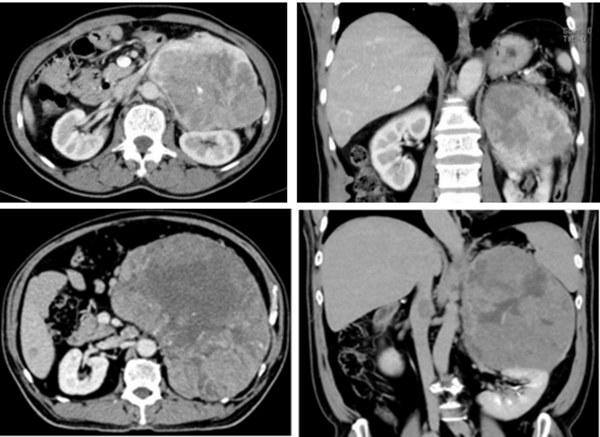

近期,医院收治的两名巨大肾上腺皮质腺癌患者中,一名68岁男性因“左腹疼痛1周”入院,检查显示患者左侧肾上腺约18×15cm巨大肿瘤侵犯肾门血管,手术难度极高。另一名56岁男性因“发现腹膜后肿物半年”入院,检查显示左肾上腺25×18cm巨大肿瘤同时累及左肾,并伴左肾静脉及下腔静脉癌栓形成,手术切除风险极大。

针对患者病情,李源教授团队联合血管外科、胆胰外科、麻醉科、代谢与内分泌科、重症医学科及肿瘤科等多学科专家进行会诊,制定了个性化手术方案。术中,团队精细操作,成功为第一例患者完整切除肿瘤及肾静脉并行左肾静脉重建术;为第二例患者实施左肾上腺巨大肿瘤切除术+左肾静脉癌栓取出术,耗时约4小时后完整切除肿瘤及癌栓,并成功为患者保留了左侧肾脏及其功能。两例患者术后均恢复顺利,后续计划至肿瘤科行下一步治疗。